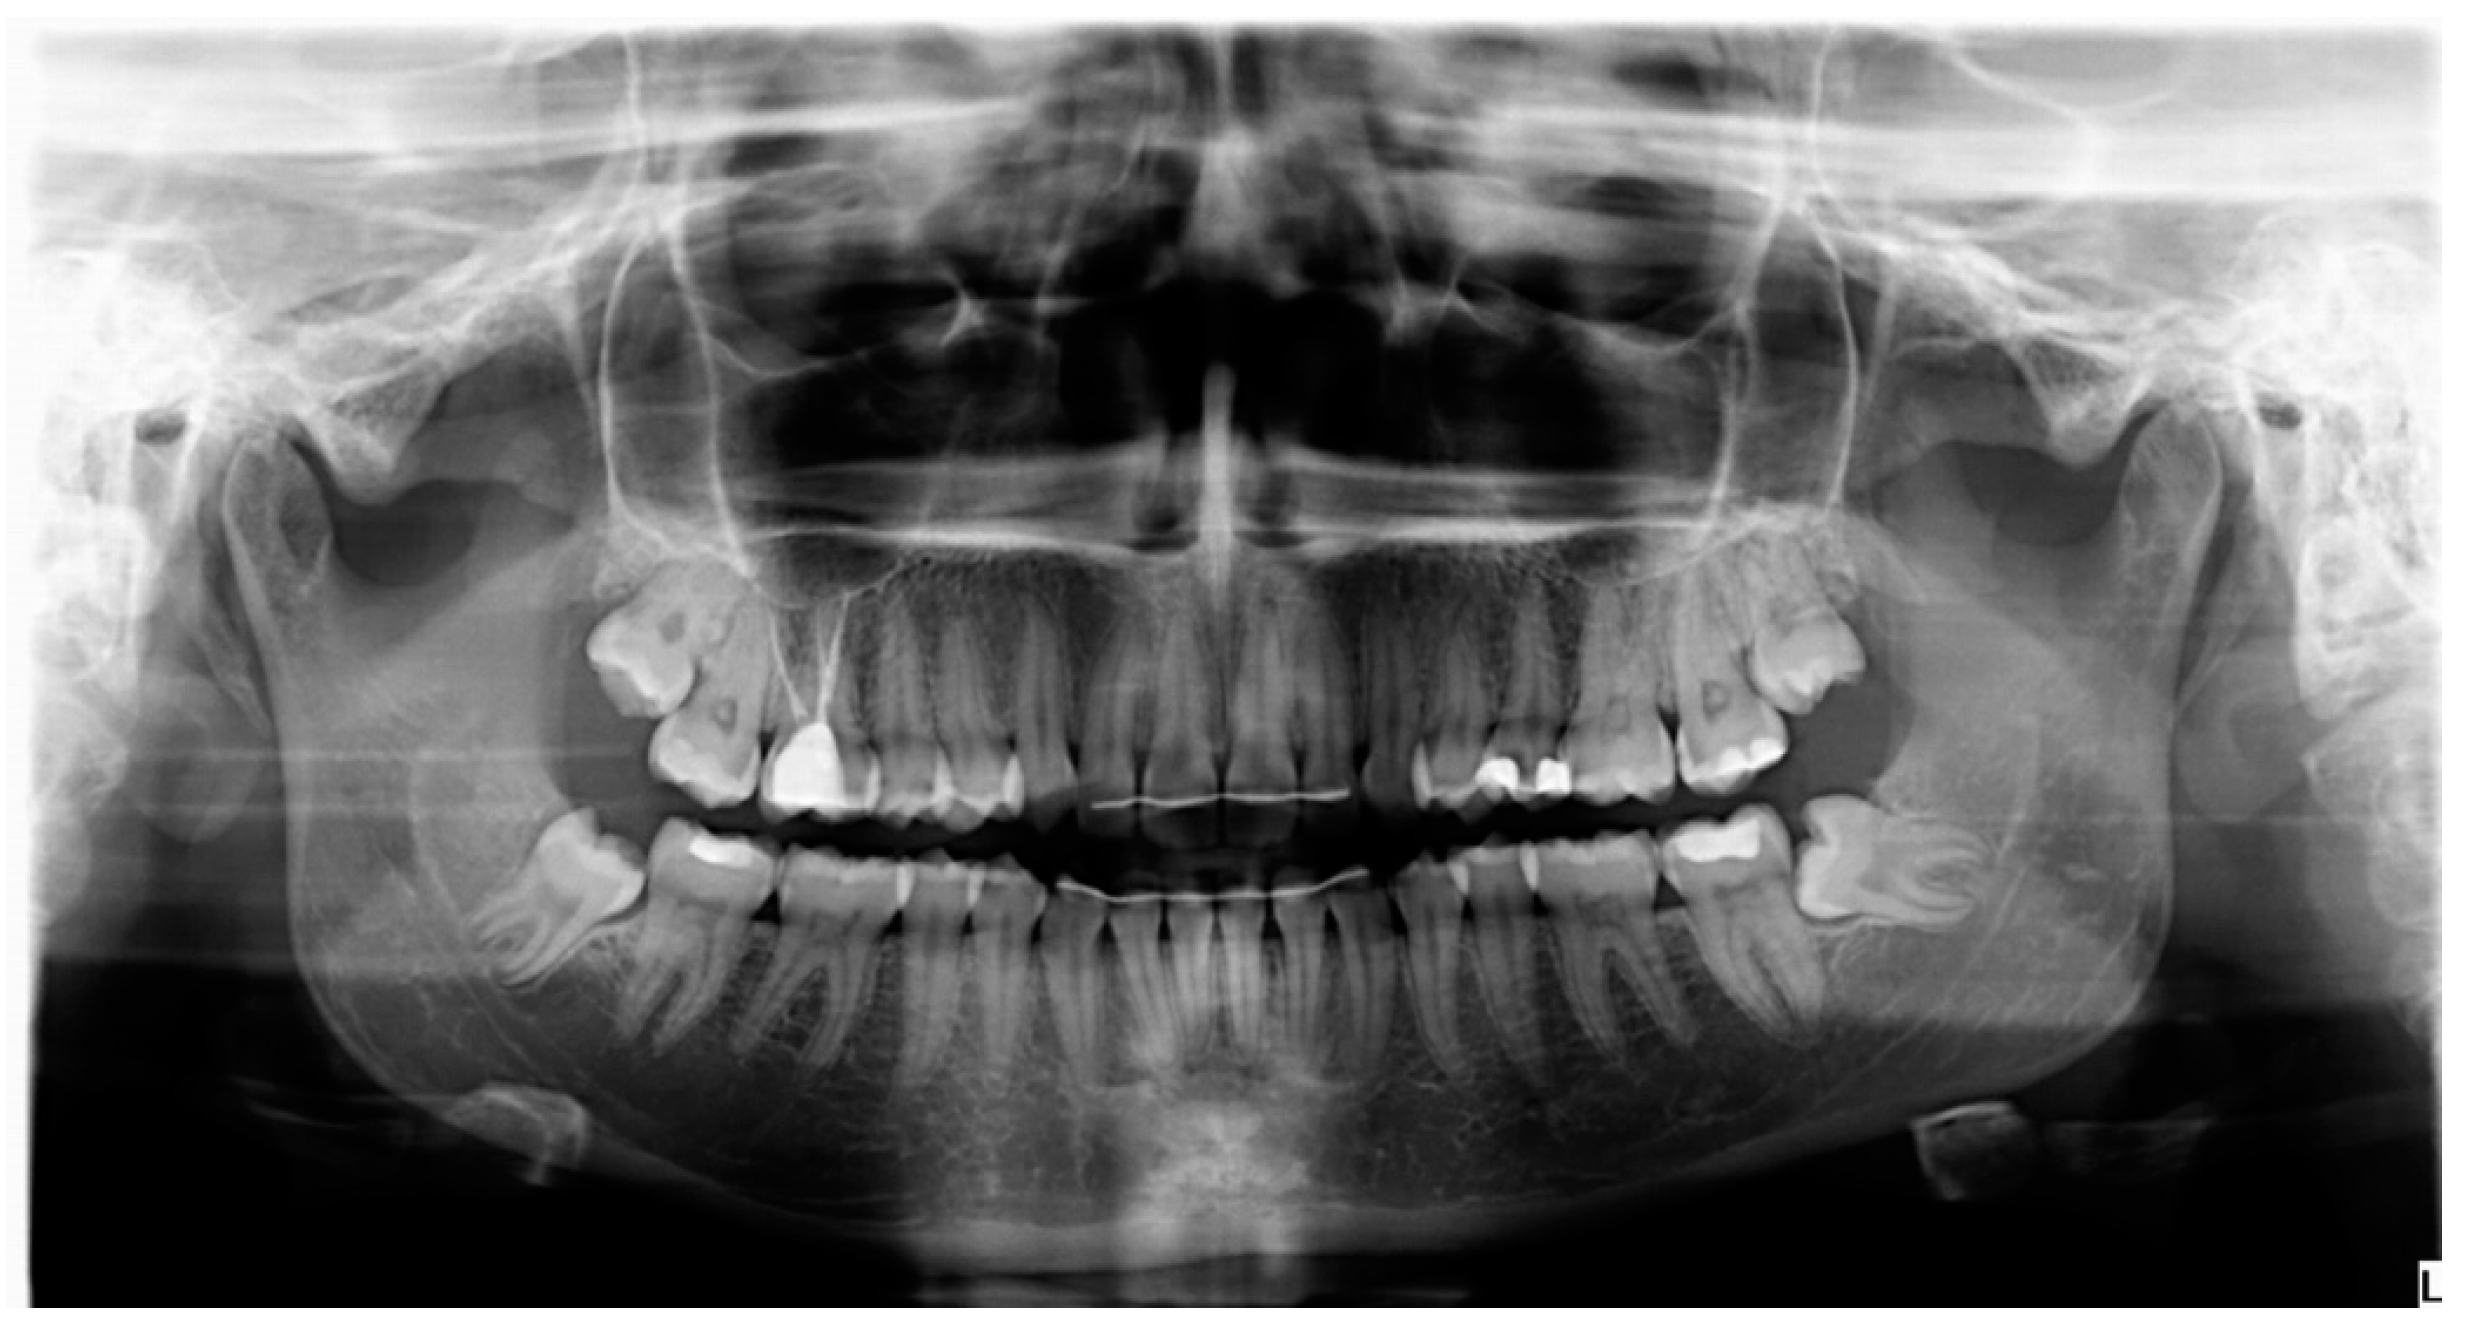

- Probing depth was measured 3 and 6 months after surgery at the DV, DM and DL points on the distal aspect of the second molar as shown in Figure 3.

- Bone density, the degree of corticalization, and crestal bone height maintenance were measured 6 months after surgery on CBCT sagittal slices in all patients (Figure 6), using the same equipment (Newtom VGI evo, QR srl-Verone, Italy).

- Distance from the IAN to the bone crest was measured at the distal aspect of the lower second molar, at the center of the third molar alveolus (Figure 9).